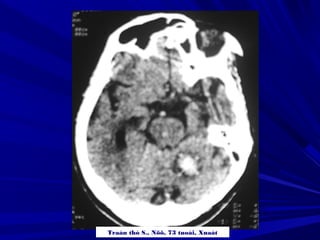

Traàn thò S., Nöõ, 73 tuoåi, Xuaát

XUAÁT HUYEÁT THAÂN NAÕOXUAÁT HUYEÁT THAÂN NAÕO

Traàn thò S.,Nöõ, 73 tuoåi, Xuaát

XUAÁT HUYEÁT THAÂNNAÕOXUAÁT HUYEÁT THAÂN NAÕO